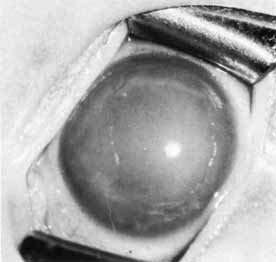

Primary congenital glaucoma presents clinically with epiphora, photophobia, and blepharospasm. Examination often reveals increased corneal diameter, corneal cloudiness (Fig. 12), and breaks in Descemet's membrane. Other findings include an intraocular pressure greater than 21 mm Hg, isolated trabeculodysgenesis on gonioscopy, and increased optic nerve cupping.

Fig. 12 Primary congenital glaucoma. Buphthalmos and corneal clouding.

A differential diagnosis of these signs and symptoms should be considered before the physician diagnoses primary congenital glaucoma. Other causes of similar corneal changes include megalocornea, metabolic diseases, corneal dystrophies, trauma, and keratitis. Epiphora or photophobia may occur in nasolacrimal duct obstruction, keratitis, iritis, trauma, and corneal dystrophies. Optic nerve anomalies simulating a glaucomatous nerve include optic pits, colobomas, and hypoplasia. Generally it is not difficult to make the diagnosis of primary congenital glaucoma when all of the signs and symptoms are considered together.